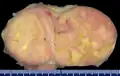

- Gross pathology of an atypical solitary fibrous tumor, evidenced by some deeply yellow necrotic areas